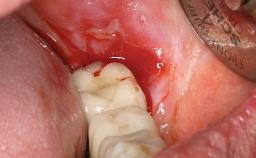

Peri-implantitis Modified by Submucosal Excess of Cement: Regenerative Peri-implantitis Therapy and Six-year Follow-up

A 30-year-old female patient was referred to the Department of Periodontology of the University of Bern, Switzerland, by a dentist in private practice. Tooth 45 had been congenitally missing and had been replaced with a titanium implant three years prior to the first visit at the Department of Periodontology. The tissue level implant had a diameter of 4.1 mm, a length of 12 mm, and a sandblasted and acid-etched (SLA) surface (Straumann® Dental Implant System; Institut Straumann AG, Basel, Switzerland). The metal-ceramic crown on implant 45 had been cemented permanently. Implant 45 had been diagnosed with peri-implantitis by the referring dentist in the course of regular supportive care.